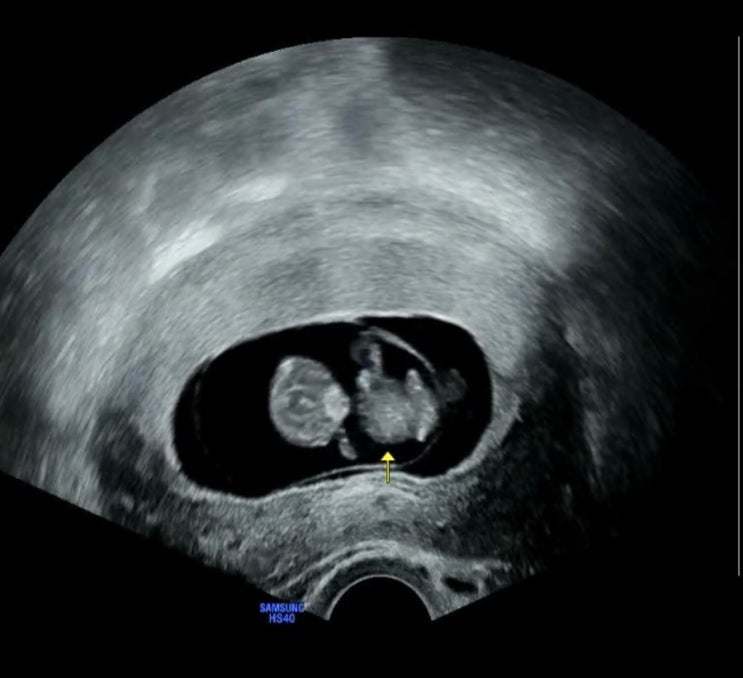

23.07.01 9주 5일, 정기검진 가다 예정일에 맞게 잘 크고 있는 둥이! 난황을 꼭 붙잡고 있는 모습이 넘 귀...